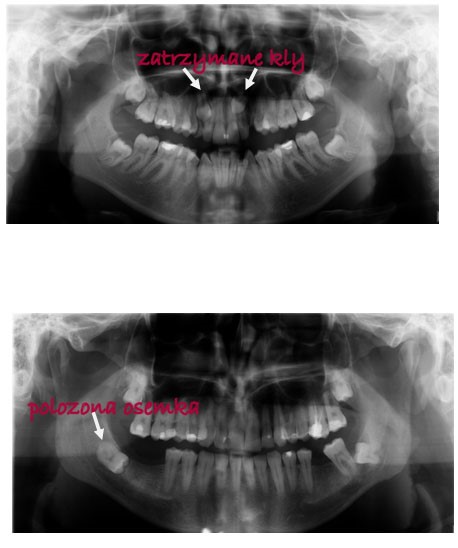

Następnie trzeba wykonać dwa zdjęcia RTG:

pantomograficzne, na którym widać zęby, kości szczęk, stawy skroniowo-żuchwowe. Sprawdzamy na nich min. obecność lub brak zawiązków zębowych jeszcze nie wyrzniętych lub zatrzymanych zębów, stan przyzębia itp.

Dodatkowe badania to np. zdjęcia rtg zębowe celowane na te okolice, które nie są zbyt czytelne w rtg pantomograficznym przeglądowym, np., gdy chodzi o zęby zatrzymane. Nowoczesna technika pozwala też wykonać zdjęcie rtg w 3D – obrazując przestrzenne ułożenie zęba w przeciwieństwie do poprzednio wymienionych, które dają obraz jednowymiarowy.